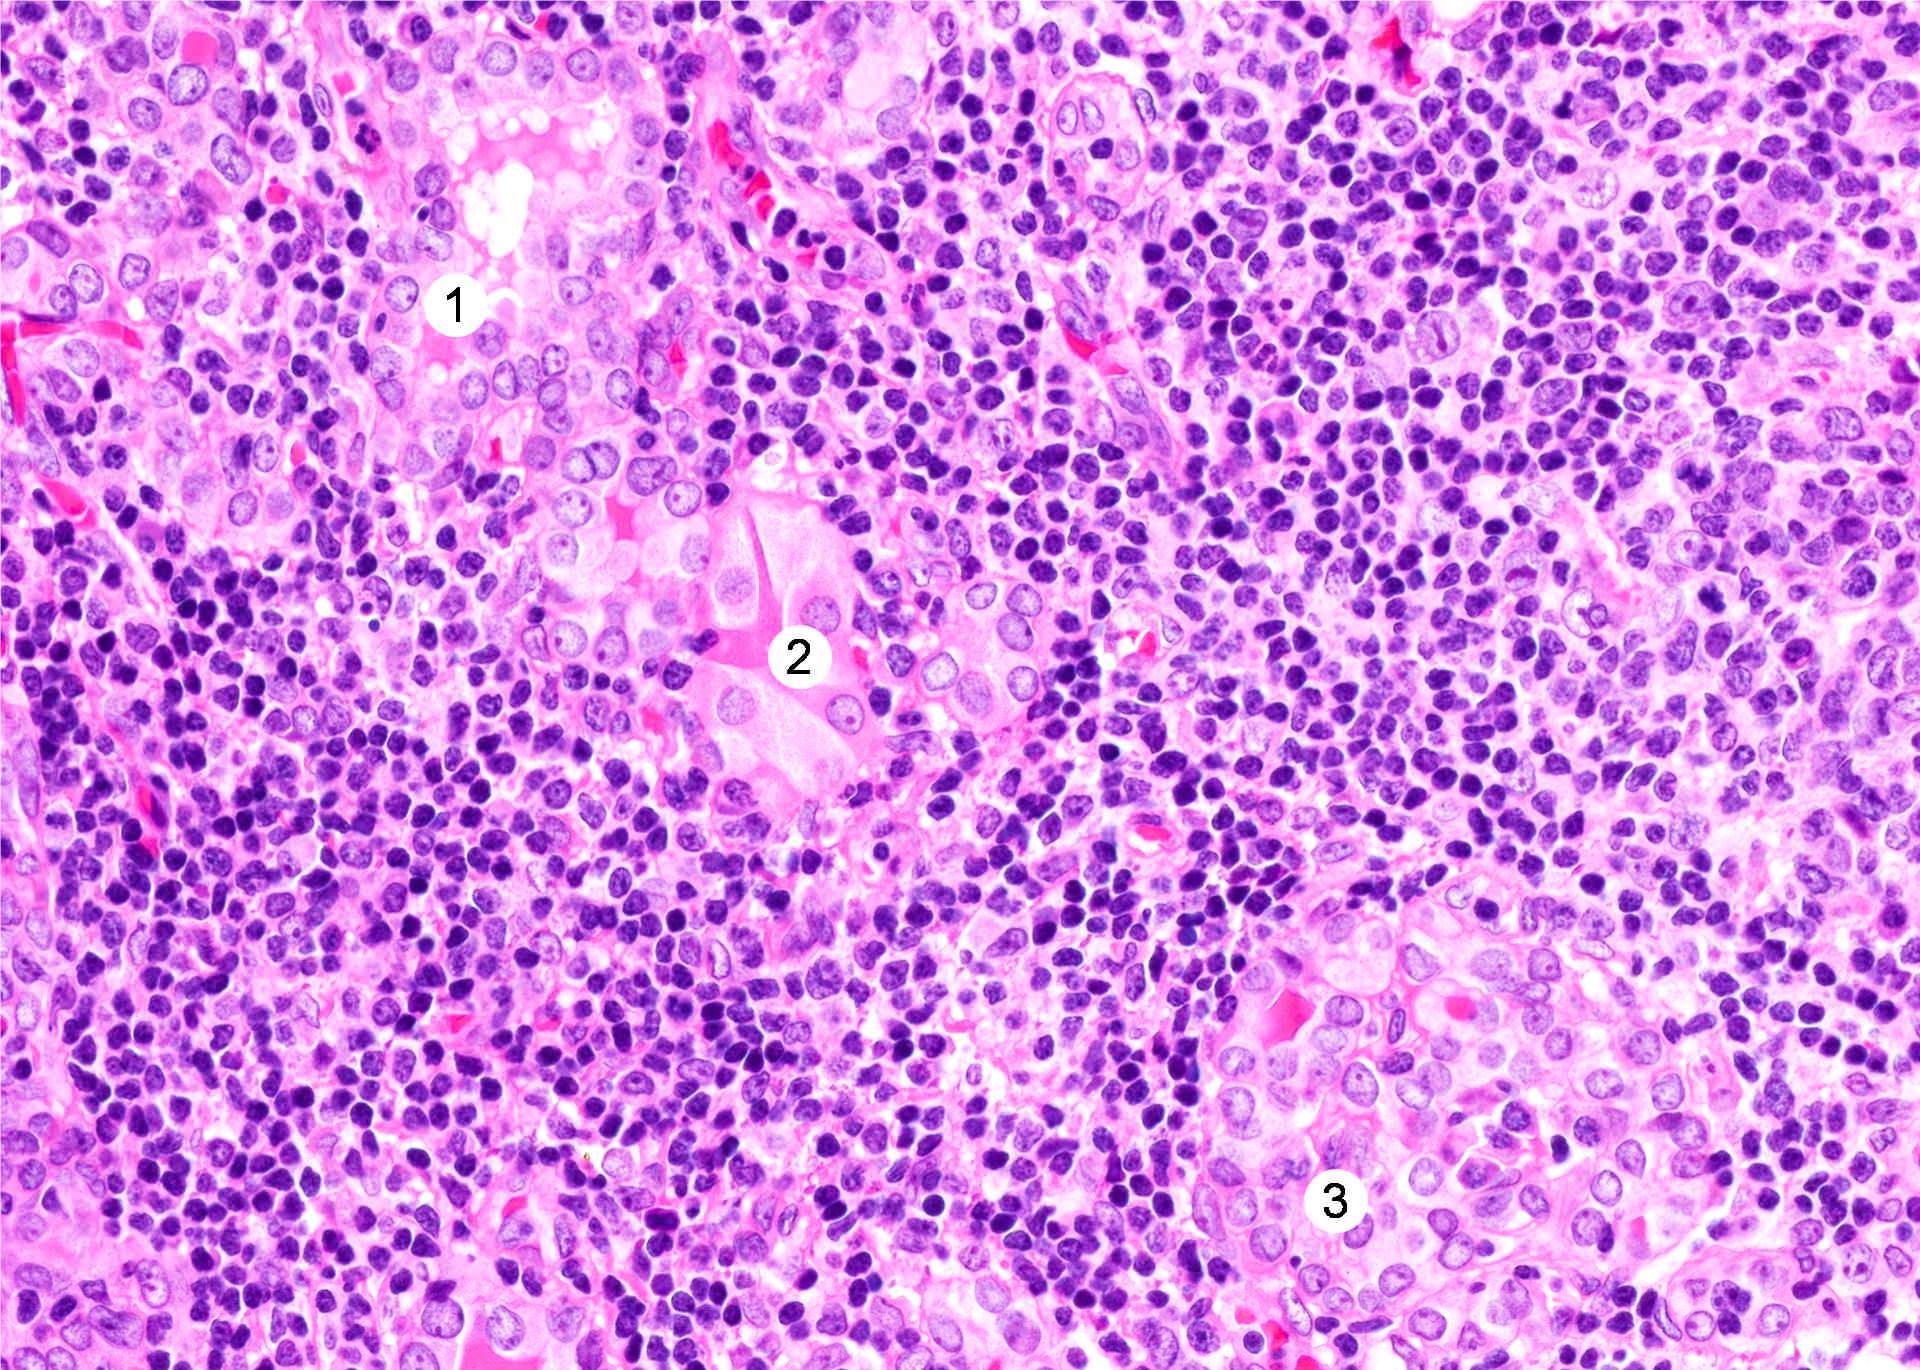

Microscopic (histologic) description

- Classic form: diffuse infiltration of thyroid parenchyma with lymphocytes and plasma cells; lymphoid follicle formation with germinal centers (Best Pract Res Clin Endocrinol Metab 2019;33:101367)

- Polymorphic lymphocytic infiltrate, predominantly T cells

- Thyroid follicular destruction

- Atrophic thyroid follicles; many lined by oncocytic cells / oncocytes having abundant granular eosinophilic cytoplasm; rarely squamous metaplasia

- Later fibrosis and nodularity (Virchows Arch 2013;462:557)

- Fibrous (or fibrosing) variant: extensive keloid-like fibrosis of thyroid parenchyma, fibrous septa divide the parenchyma into lobules, mononuclear cell infiltration, lymphoid follicles, thyroid follicular atrophy, oncocytic cell and squamous metaplasia (Autoimmun Rev 2014;13:391)

- IgG4 related variant: dense lymphoplasmacytic infiltrate, enriched in IgG4 producing plasma cells (> 20 cells per high power field); interstitial fibrosis; often associated with obliterative phlebitis (Autoimmun Rev 2014;13:391)

- Juvenile thyroiditis, Hashitoxicosis and painless thyroiditis: rare / absent germinal center formation and follicular atrophy, follicular cell hyperplasia, less pronounced oncocytic cell metaplasia and fibrosis (Autoimmun Rev 2014;13:391)

- Variable atypia of follicular cells and oncocytic cells, may mimic and act as a precursor (limited evidence) of papillary thyroid carcinoma (Endocr Pathol 2021;32:368)

- Squamous metaplasia of follicular epithelium can be confused with solid cell nests (J Clin Endocrinol Metab 2012;97:2209)

- May be associated with colloid goiter, follicular neoplasm, oncocytic cell neoplasm, papillary thyroid carcinoma and primary thyroid lymphoma (Acta Cytol 2009;53:507, Front Oncol 2017;7:53)

Microscopic (histologic) images

Contributed by Andrey Bychkov, M.D., Ph.D. and Shipra Agarwal, M.D.